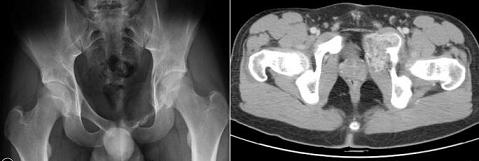

La sintomatologia è di solito rappresentata da tumefazione e dolore, peraltro di grado lieve, la struttura ossea interessata assume un aspetto osteolitico marcato, talora rilevante, le fratture patologiche sono rare.

Le suddette lesioni presentano una ipervascolarizzazione patologica rifornita da uno o più vasi e sono caratterizzate dalla presenza di cavità incluse ripiene di detriti cellulari e sangue, separate da setti connettivali, sono tipici i livelli liquidi ben visibili alla TC ed alla RM.

Adolescente di 16 anni.